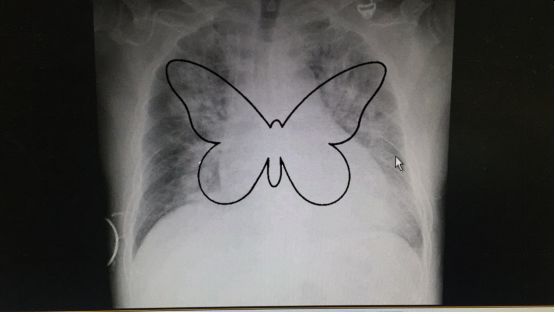

肺门蝴蝶影

蝶翼征都是心衰肺水肿不还要和这些病鉴别

pcp影像学:以肺门为中心,蝴蝶状,不累及胸膜

以双侧肺门为中心对称分布的大片状致密影,肺门区密度较高,边缘模糊

病灶为广泛的两侧对称性密度增高影,靠近肺门最明显,肺野周围部则逐渐

图 3 全胸片示心影增大,典型「蝴蝶影」,双侧肋膈角钝模糊,提示心衰

是指尿毒症时胸部x线片上呈现以肺门为中心,向两侧放射的对称型蝴蝶